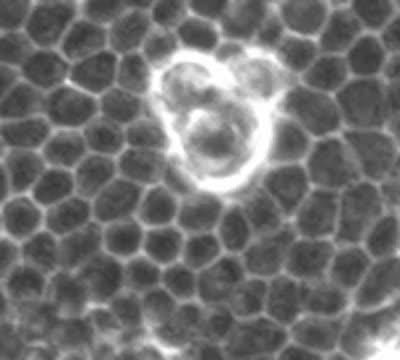

Transformed Cells Becoming Extruded

video: The movie shows transformed cells become extruded after losing a competition against surrounding normal cells. The study suggests the surrounding cells influence the metabolism of transformed cells during the elimination process. view more

Credit: Hokkaido University

Most cancers begin when one or more genes in a cell mutate. These newly "transformed" cells get extruded and eliminated after losing a competition against the surrounding normal cells in the epithelium, or the outer layer of the body. However, the mechanism by which normal cells recognize and attack the transformed cells remains elusive.

A research team led by Professor Yasuyuki Fujita of Hokkaido University's Institute for Genetic Medicine explored this natural defense mechanism using cultured mammalian cells and a mouse model. The study uncovered two metabolic changes occurring in the newly transformed cells: mitochondrial dysfunction and an elevated glucose uptake. The changes were significant only when the transformed cells were surrounded by normal epithelial cells, indicating that the changes are induced by the normal cells. Furthermore, according to the study, the metabolic changes play an important role in eliminating the transformed cells.